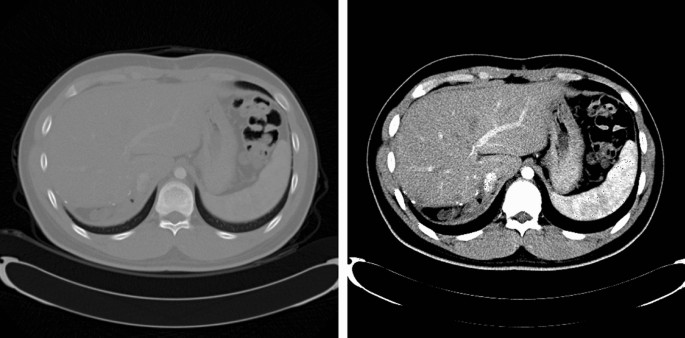

In this study, the window level and window width were set to clearly observe the liver on CT (window level: 50, window width: 180)23. Figure 1 shows the result of the window setting. Furthermore, CT data had the same 512 × 512 in-plane resolutions, but due to the computational limitation of the graphics card, the image was resized to a resolution of 256 × 256. Finally, the image and ground truth data had a shape of 64 × 256 × 256 × 1 and were divided into train: validation: test sets in the ratio of 70: 15: 15.

Comparison between the raw computed tomography axial view images (left) and with the window setting (right).